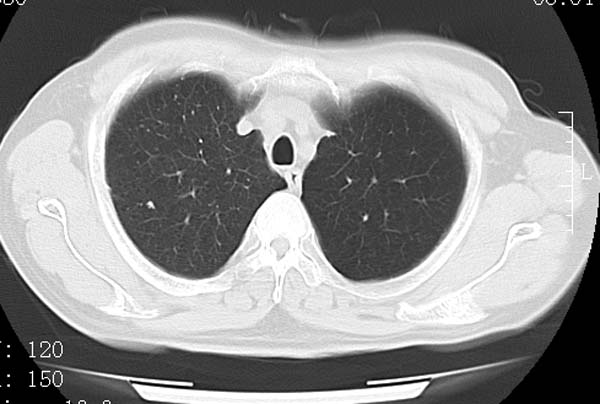

以下是引用守望可可西里在2008-6-24 1:11:00的发言:[br][br] 考虑为周围型肺癌:[br] 1.分叶结节,形态极不规则,蟹足样伸展的恶性浸润特征比较明确。[br] 2.磨玻璃影中由多个更高密度小结节聚集呈梅花瓣样。[br] 3.局部胸膜凹陷征比较明确。[br][br] 另:纵隔胸膜明显增厚、粘连。

以下是引用zjzjr在2008-6-24 11:19:00的发言:[br]支持左下肺周围型肺癌伴右肺转移,纵隔淋巴结转移,心包积液.

以下是引用zhangling在2008-6-24 14:56:00的发言:[br]我们科室意见报告为[br][br]1考虑左下肺周围型肺癌[br]2右肺小结节考虑转移瘤,纵隔淋巴结转移[br]3心包积液. [br] 各位老师分析的相当好 谢意[br]